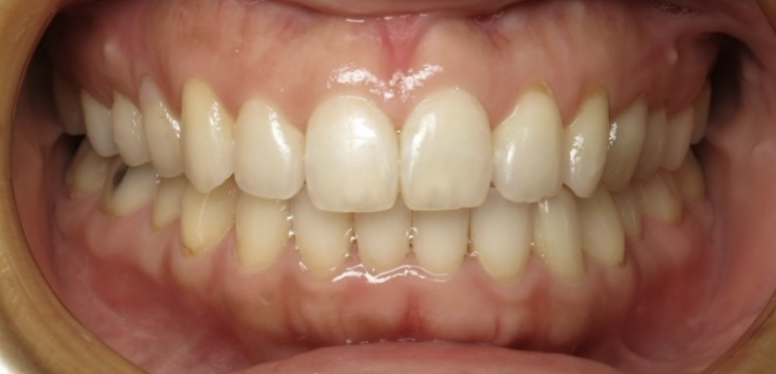

Before

After

Corrected with invisalign